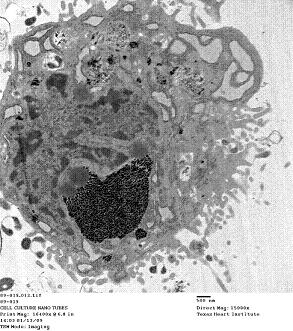

| Dark spots are aggregates of gadonanotubes (GNTs) in the cytoplasm of a mesenchymal stem cell. Tests show GNTs are highly effective for tagging and tracking stem cells through magnetic resonance imaging. (Credit: Lesa Tran/Rice University) |

Houston, TX | Posted on November 12th, 2010The study has determined GNTs are effective in helping doctors track stems cells through the body by making them 40 times better than standard contrast agents used in magnetic resonance imaging. Contrast agents help doctors spot signs of disease or damage in MR images.

Researchers at Rice and the Texas Heart Institute at St. Luke's Episcopal Hospital in Houston reported in the journal Biomaterials that mesenchymal stem cells drawn from pig bone marrow labeled with GNTs are easily spotted under MRI. The technique holds promise for tracking the progress of tagged cells as they travel through a patient's body.

However, GNTs can. Invented in the lab of Rice chemistry professor Lon Wilson in 2005, the nanotubes sequester bundles of gadolinium ions, which enhance contrast in MRIs but cannot escape their carbon cages. This makes them biologically inert and safe for tagging cells from within.

The team found GNTs did not affect the stem cells' ability to differentiate into other types of cells or to self-renew, though work continues to characterize their ability to adhere to cell scaffolds under various conditions.